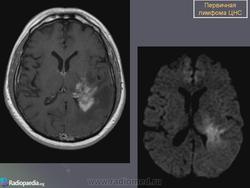

Первичные лимфомы ЦНС. Вс, 22/05/2011 - 21:45 #1 Катенёв Валенти... Не на сайте Был на сайте: 7 лет 5 месяцев назад Зарегистрирован: 22.03.2008 - 22:15 Публикации: 54876 Продолжение.Приложения:

Продолжение.